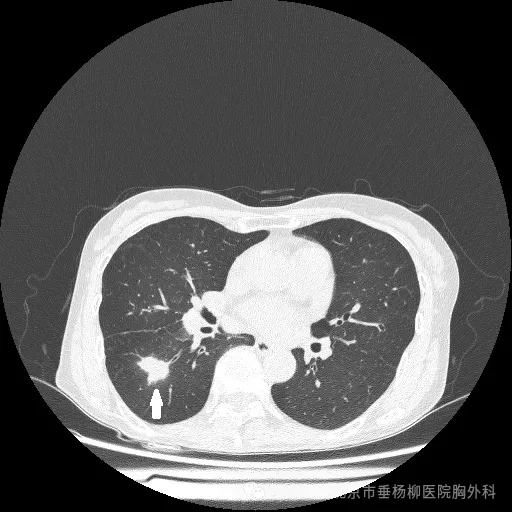

2017.5影像图

我科近期接诊的一名患者就是一个深刻的教训。该患者在2017年5月首次体检时发现肺部存在磨玻璃结节,大小约8.1X5.3毫米,但因对病情重视不足,未能坚持定期复查。直到今年复查时,才震惊地发现肺部结节已增长至23X19毫米,并通过PET-CT检查高度怀疑为恶性肿瘤,且已出现纵隔淋巴结转移,失去了手术切除的最佳时机。这一案例不仅令人痛心,更提醒我们一旦发现肺部磨玻璃结节,必须立即引起高度重视,并尽快前往正规医疗机构接受专业的诊断和治疗。